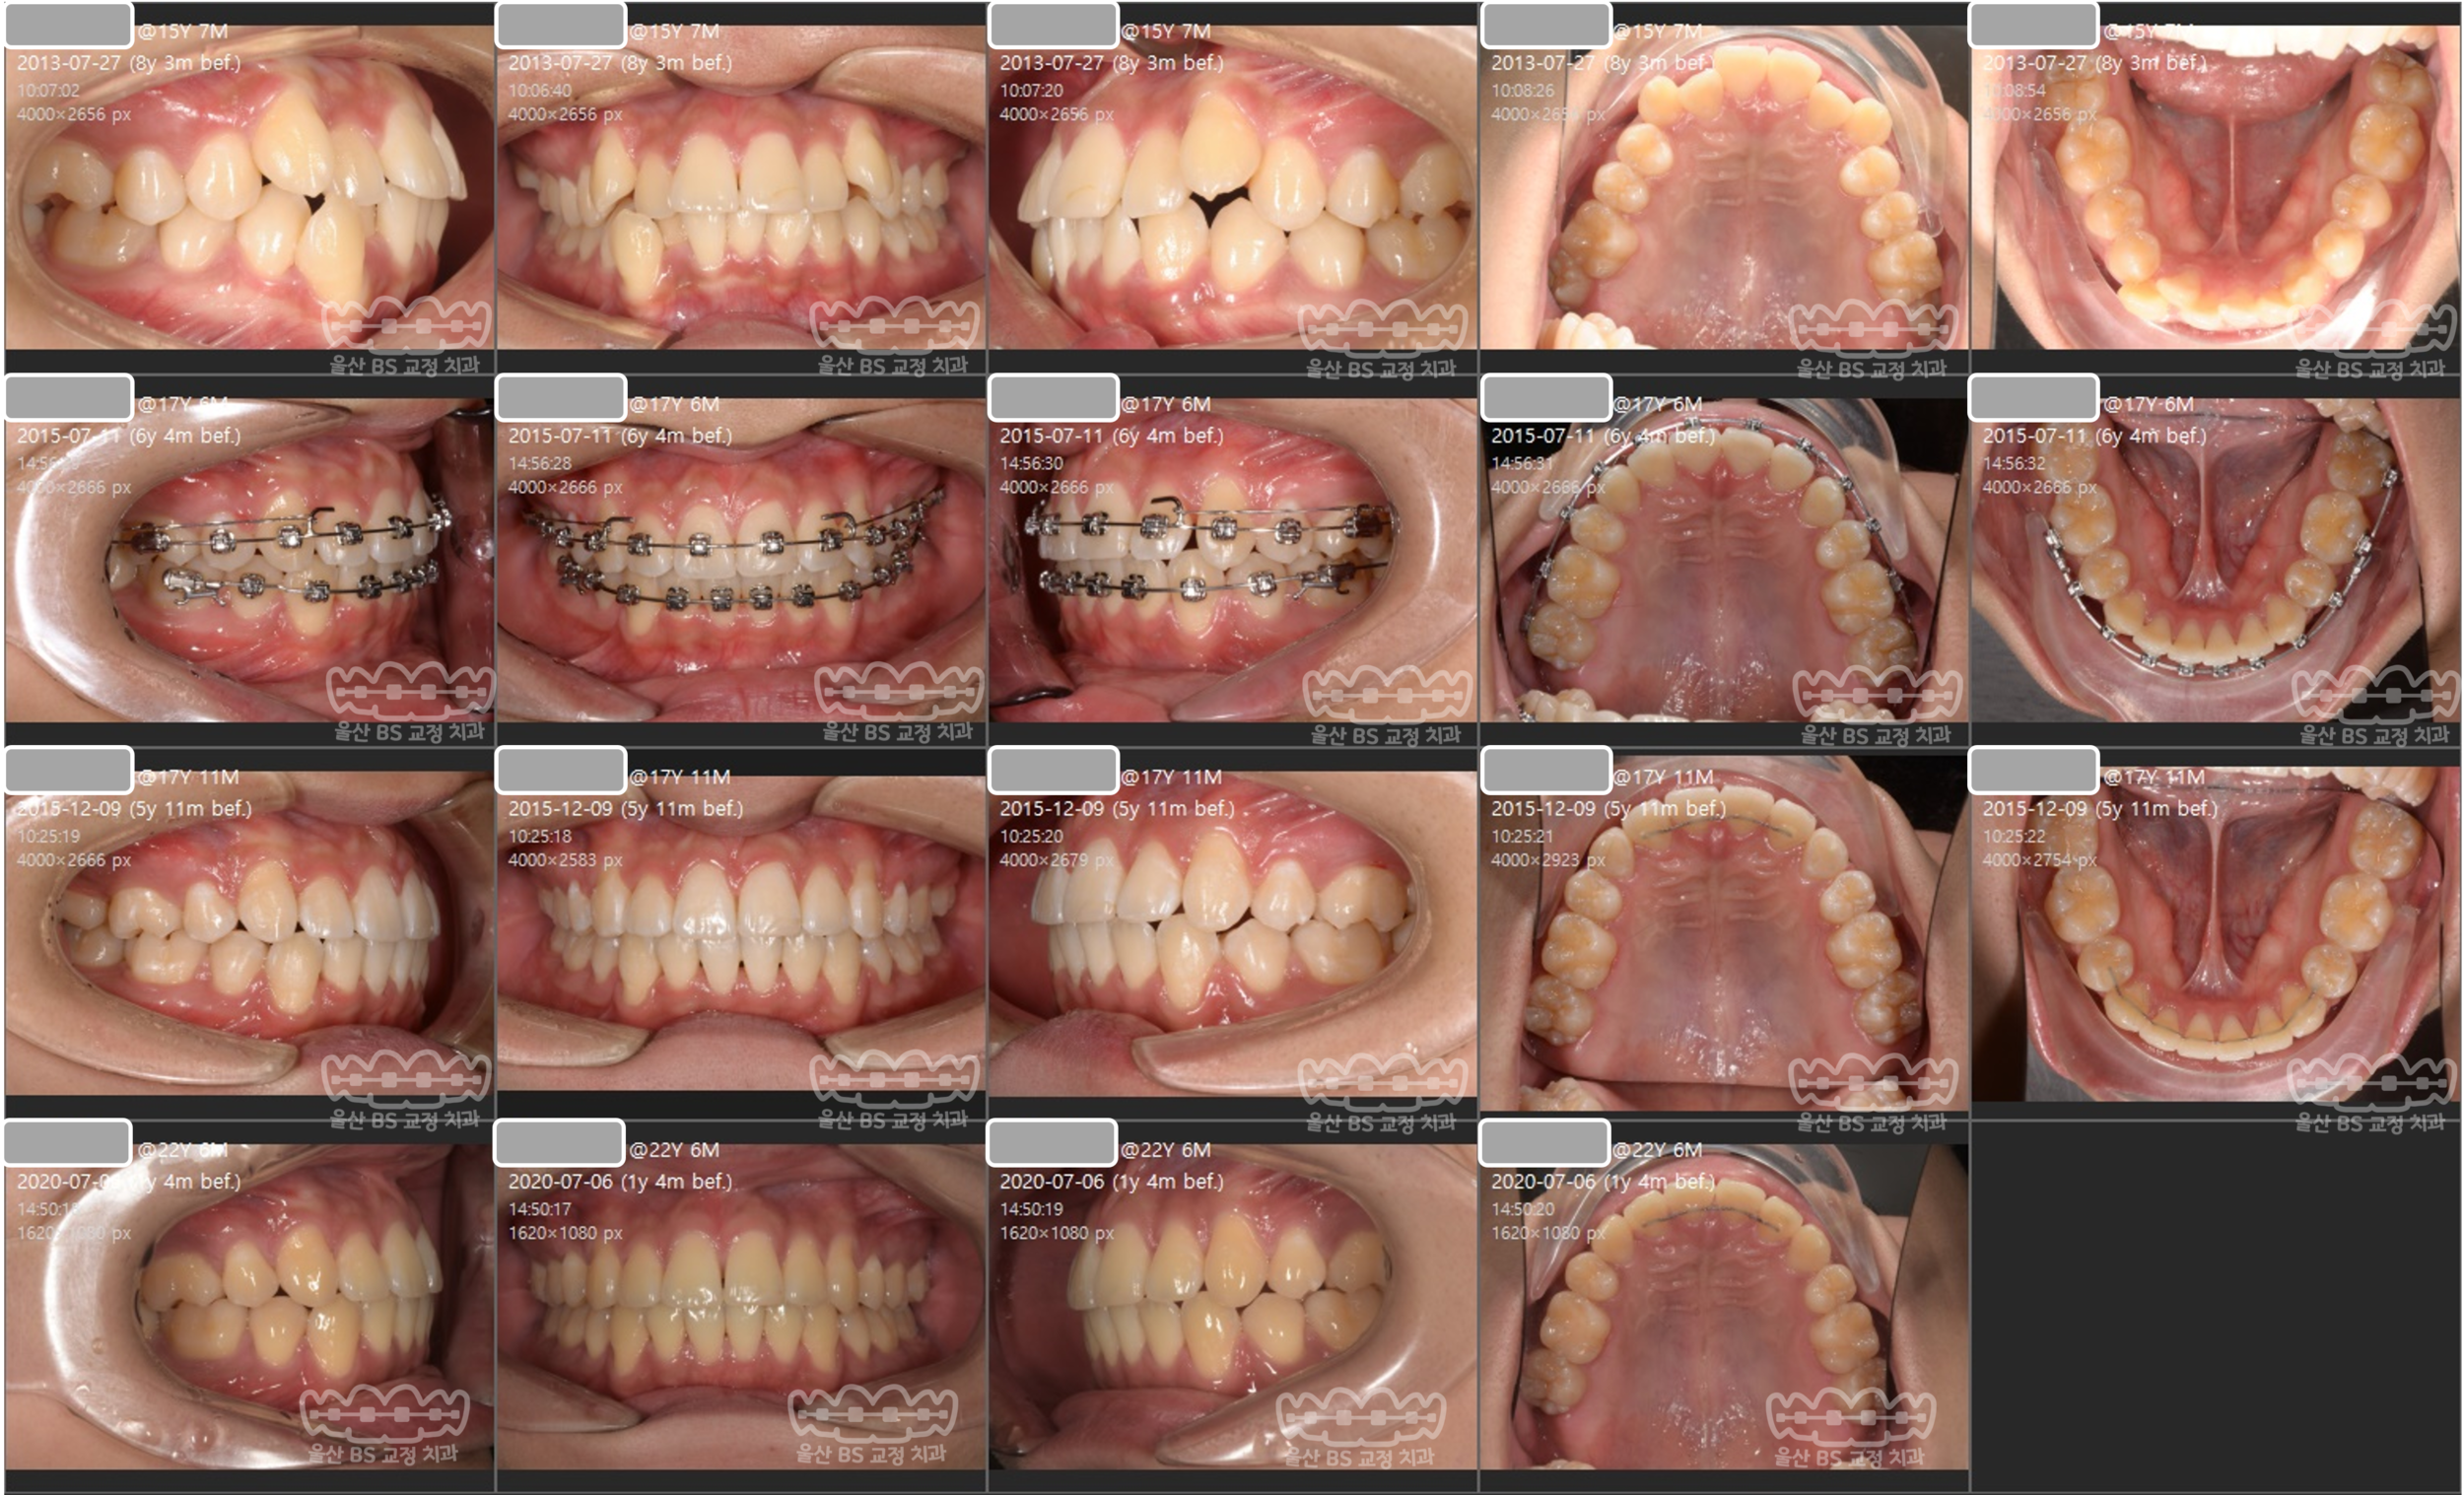

돌출입을 해결하기 위해 2년간 교정치료를 진행하였습니다. 교정 치료 완료 후 6년이 지났지만 치열은 가지런한 상태를 유지하고 있습니다. 교정 치료 기간에는 치아가 썩는것을 방지하기 위해 적극적으로 구강 위생 관리와 교육을 하여 비교적 밝은 치아 색을 유지하고 있지만, 교정 치료가 완료 된 후 1년에 한번 정도만 내원하는 과정을 거치는 동안 구강위생 체크가 부족하여 치아는 전반적으로 노란색으로 변색된것을 볼 수 있습니다. 이러한 변색은 미백 치료를 하거나 평소에 양치질을 열심히 하시면 돌아오게 됩니다.

불규칙한 치열을 가진 경우라 하더라도 유지장치를 잘 사용하면서 매년 1회 정도 병원에 내원하여 관리한 경우입니다. 2년의 교정 치료 이후 5년이 지났지만 불규칙한 치열로 돌아가는 재발은 발생하지 않았습니다. 발치한 공간이 벌어지지도 않고 잘 유지되고 있습니다.

교정치료기간 2년을 넘기지 않고 비교적 빠르게 불규칙한 치열이 해결된 경우입니다. 이러한 경우라도 적극적인 유지관리를 할 경우 수년의 시간이 지나도 치열이 재발되지 않고 잘 유지되는것을 볼 수 있습니다.